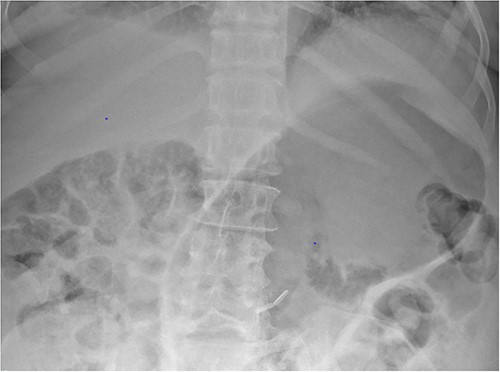

Based on the clinical and radiological picture, acute gastric dilatation was diagnosed, presumed secondary to a combination of opioid analgesia and gastric dysmotility from Parkinson’s disease. A nasogastric tube was introduced, intravenous fluids were given, and a venous blood gas was performed, which showed pH of 7.46 and lactate 1.0 mmol/L. An urgent CT scan of the abdomen and pelvis with intravenous contrast was performed; this demonstrated there had been interval reduction of the portal venous gas (Fig. 3), with only minor residual gas seen at the periphery of the left lobe of the liver and the gastric fundal wall. No other radiological features of visceral ischaemia within the abdomen were observed, with the coeliac axis and the collaterals from the phrenic arteries and superior mesenteric artery all patent.

CT abdomen and pelvis image demonstrating interval resolution of portal venous gas, at the level of T11/12.